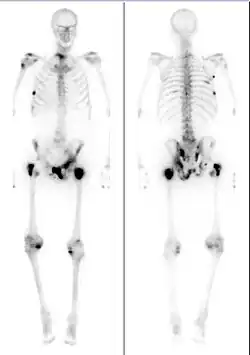

The extent of cancer spread is assessed by MRI or PSMA scan – a positron emission tomography (PET) imaging technique where a radioactive label that binds the prostate protein prostate-specific membrane antigen is used to detect metastases distant from the prostate.[30][24] CT scans may also be used, but are less able to detect spread outside the prostate than MRI. Bone scintigraphy is used to test for spread of cancer to bones.[30]